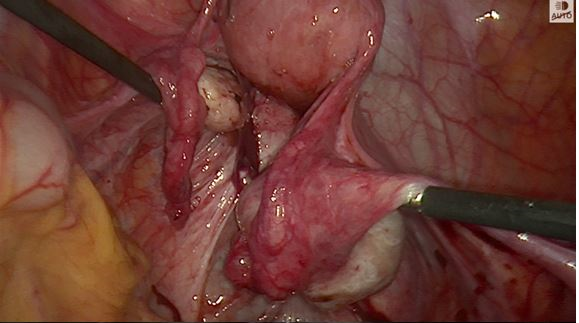

Figure 1A

Path of ureters at the start of endometriosis surgery

In the past I often had to dissect out the ureter and place a rubber sloop or even consider a ureteric stent but both of these procedures can cause trauma to the ureter. However slooping will only help identifying a portion of the ureter whereas ICG can show the entire length of pelvic ureter (figures 1A and 1B below). Stenting can lead to post-operative pain and haematuria and I don’t find them particularly helpful in identifying the ureter prior to seeing the stent when you transect the ureter!